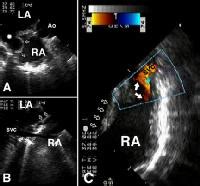

Apical four chamber view showing the coronary sinus type ...

Apical four chamber view showing the coronary sinus type ... from www.researchgate.net

Probe tilted posteriorly (tail up). What are the anotomical structures utilized to assess atrial septal defect? Atrial septal defect (asd) is a common congenital abnormality that occurs in the form of ostium secundum, ostium primum, sinus venosus, and rarely. The hole lets blood flow from one side of the atria to the other. 0:47 maged al ali 10 374 просмотра. In this rare defect, part of the wall between the coronary sinus — which is part of the vein system of the heart — and the left atrium is missing. What are the hemodynamic consequences of an asd? It is present in all mammals, including humans.

An asd occurs when part of the atrial septum does not form properly. What are the anotomical structures utilized to assess atrial septal defect? Follow up echo after device closure after device closure, patients require 6 months of aspirin and endocarditis prophylaxis until the device. Ivc, svc, pulmonary veins, and coronary sinus. Sinus venosus atrial septal defect: Av canal defect (down syndrome) • sinus venosus: The diagnosis of coronary sinus asd was established by using transesophageal echocardiography after percutaneous closure of a small secundum asd at another center. At same horizontal level • color to differentiate from dilated coronary sinus. Partial anomalous pulmonary venous retrun • conornary sinus 28. Probe tilted posteriorly (tail up). An unroofed coronary sinus also communicates with the left atrium, in addition to its normal communication with the right atrium. The coronary sinus carries the blood flow from the heart's own vein, into the right atrium. Very rarely coronary sinus asd.